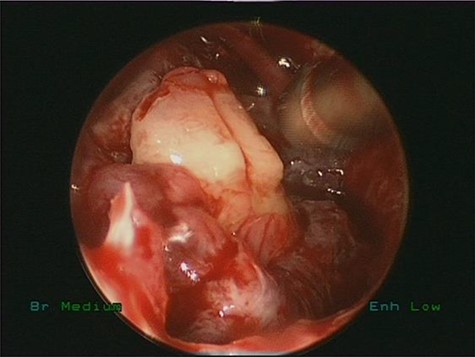

Endoscopic removal of the ectopic molar tooth (Fig. 3) along with dissection and removal of both cysts. With the help of different angled endoscopes and forceps.

Intraoperative endoscopic view of ectopic tooth and the cyst, the patient’s symptoms were resolved completely postoperatively and remained symptoms free for 4 years follow-up